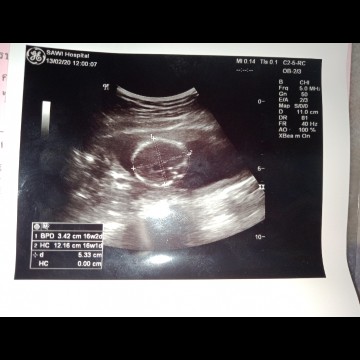

วันนี้ไปอัลตร้าซาวด์ครั้งแรก ท้องแรกไม่รู้เค้าดูยังไง เพศยังไม่เห็นใช่ไหมค่ะ คุณแม่บ้านไหนคลอดเดือนกรกฎาบ้างค่ะ เม้นกันหน่อย

ส่วนนี้น่าจะหัวนะคะ คุณหมอเราจะบอกค่ะว่าเพศอะไรถ้าเห็น